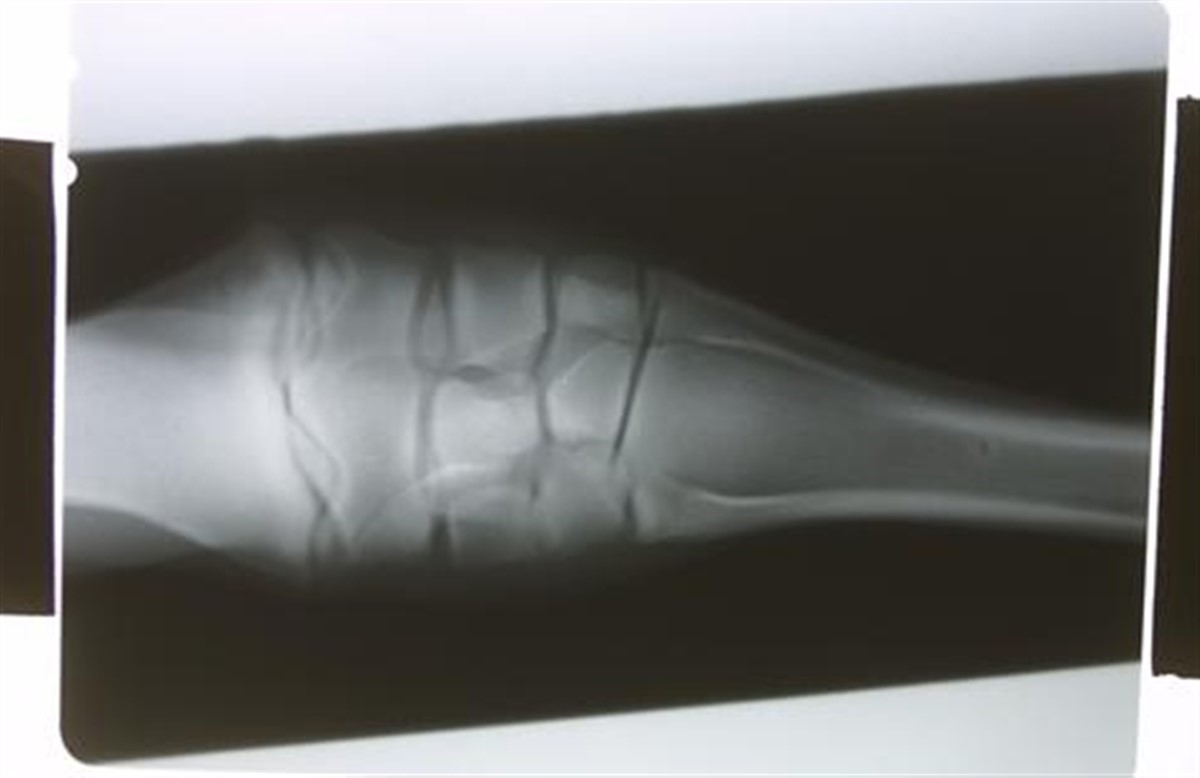

Under 2011 American Association of Equine Practitioners konventionen den 18. - 22. november i USA fortalte John Janicek fra Weems and Stephens Equine Hospital om studiet af 398 heste, der havde haft brug for en gips-forbinding, fx i forbindelse med frakturer. Studiet viste blandt andet følgende: - hestene havde oftere gips på bagben end forben. - skader i blødt væv (sår, skader på sener/ledbånd) blev forbundet med gips oftere en skader på hårdt væv (frakturer). - 45% fik sår fra gipsen og hos 5% gik gipsen i stykker. Kilde: The Horse